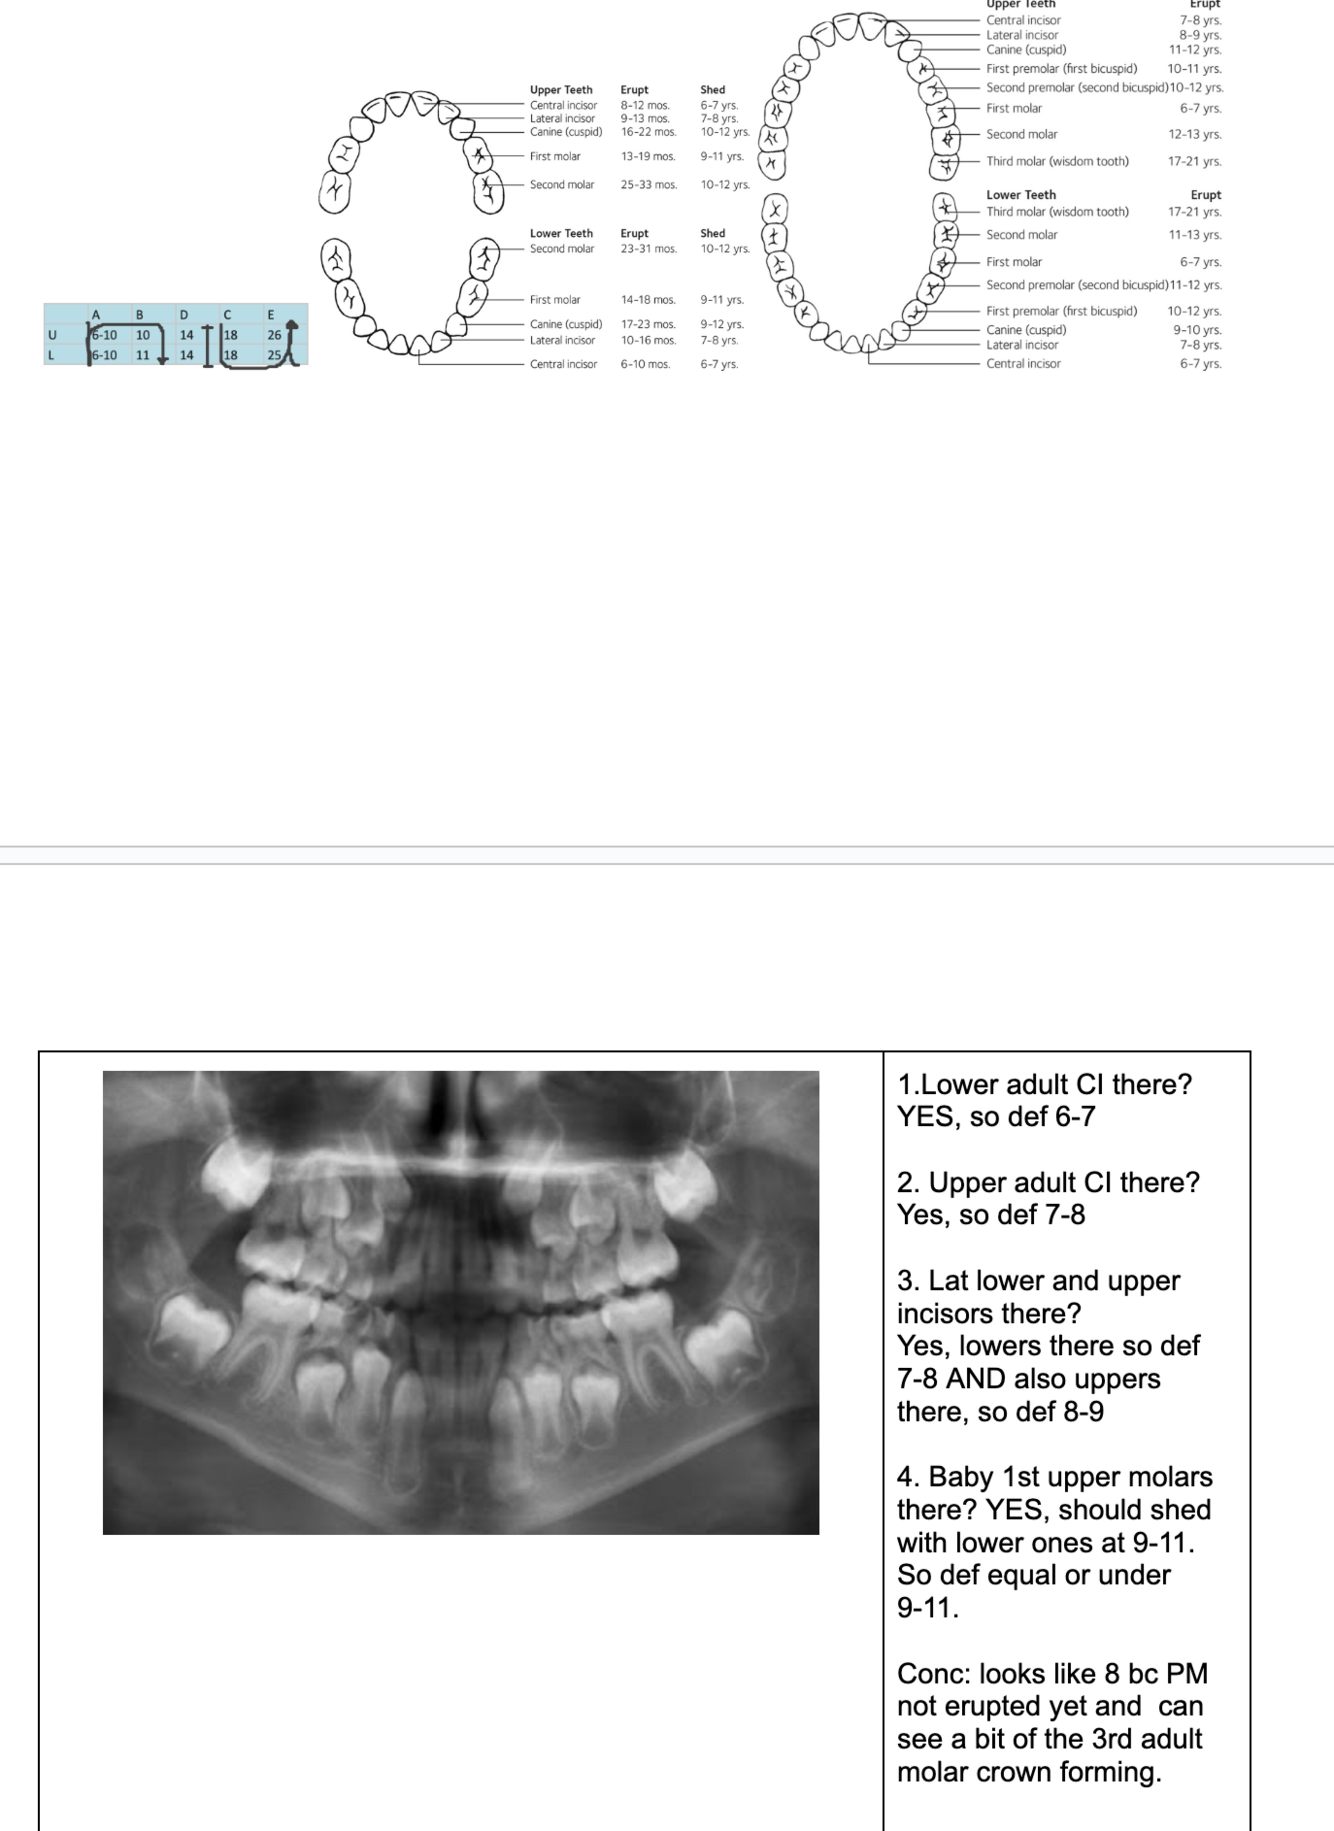

Eruption Dates Flashcards

(24 cards)